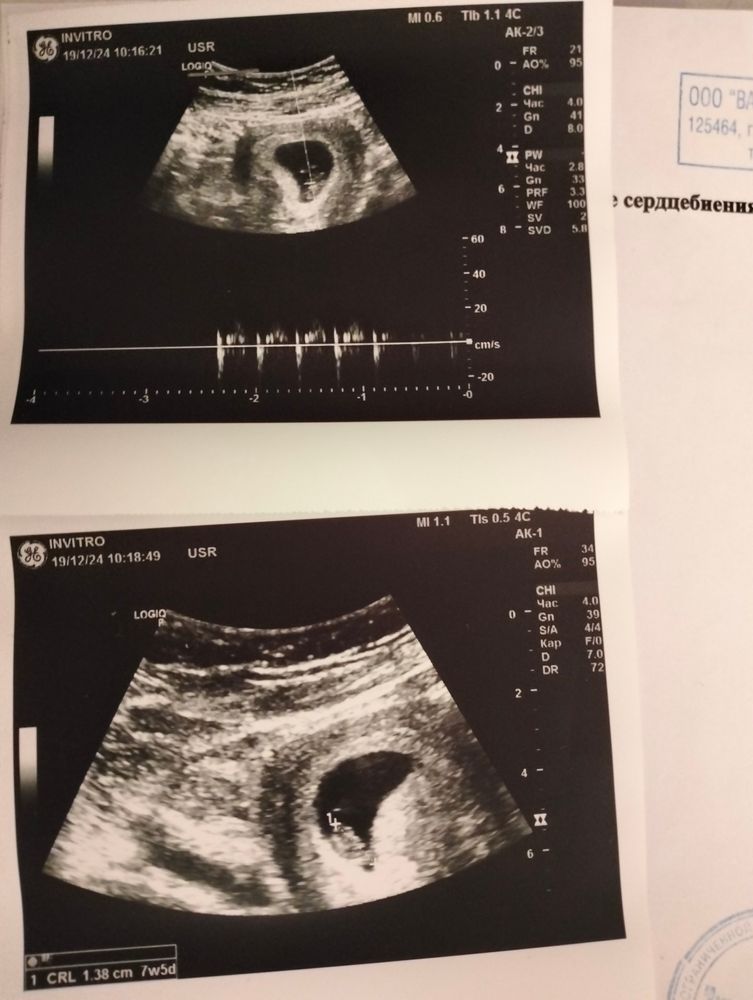

Как боролись вы и боролись ли? Я в страшном смятении, стоит ли вступать на тропу Утрожестана. Ни болей, ни выделений нет, просто по УЗИ проверилась. УЗИ прилагаю - без понятия, что делать в этой ситуации. Может вообще лежать и не пичкать себя лишним - на следующей неделе к платному гинекологу пойду, а пока хочу услышать ваш опыт🙏